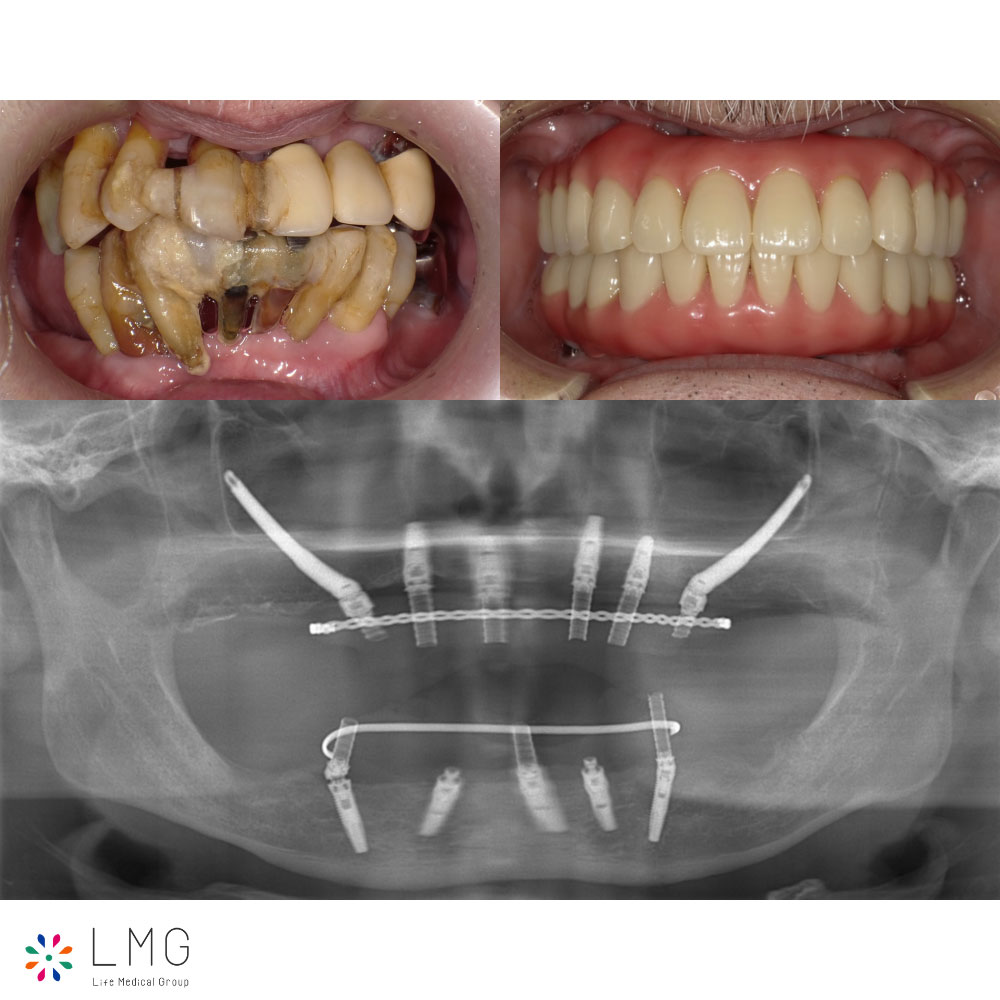

ザイゴマインプラント治療 「ザイゴマインプラント治療」を行われた患者さまのビフォーアフターをご紹介します。 ※ご紹介している症例は、あくまでも患者様固有の症例ですので、実際には患者様によって治療期間や、治療法など個人差が […]